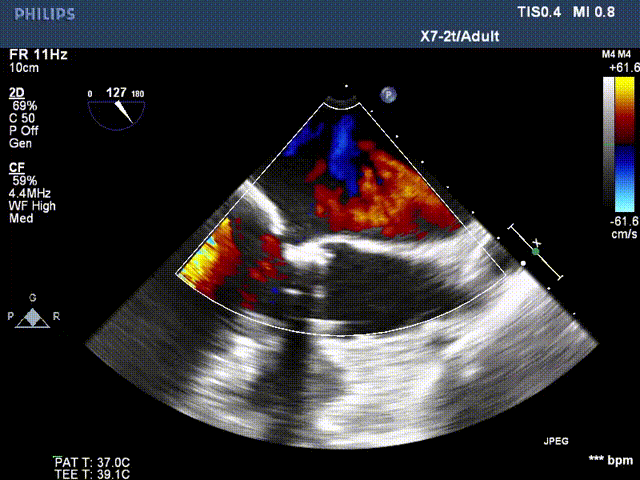

患者二尖瓣机械瓣瓣周可见两处间隙,分别位于10点位、1-2点位,大小分别约为:10点位7×5mm,1-2点位10×4mm,彩色血流提示二尖瓣位瓣周返流(两束,大量),主动脉瓣位机械瓣上血流速度正常,瓣周未见明显返流。

心脏超声可见两处二尖瓣瓣周漏